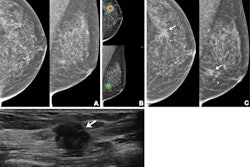

- Very low-dose imaging exams such as mammography and radiography, excluding imaging of the abdomen and pelvis, do not require pregnancy verification. The same goes for CT imaging outside the abdomen and the pelvic/hip area.